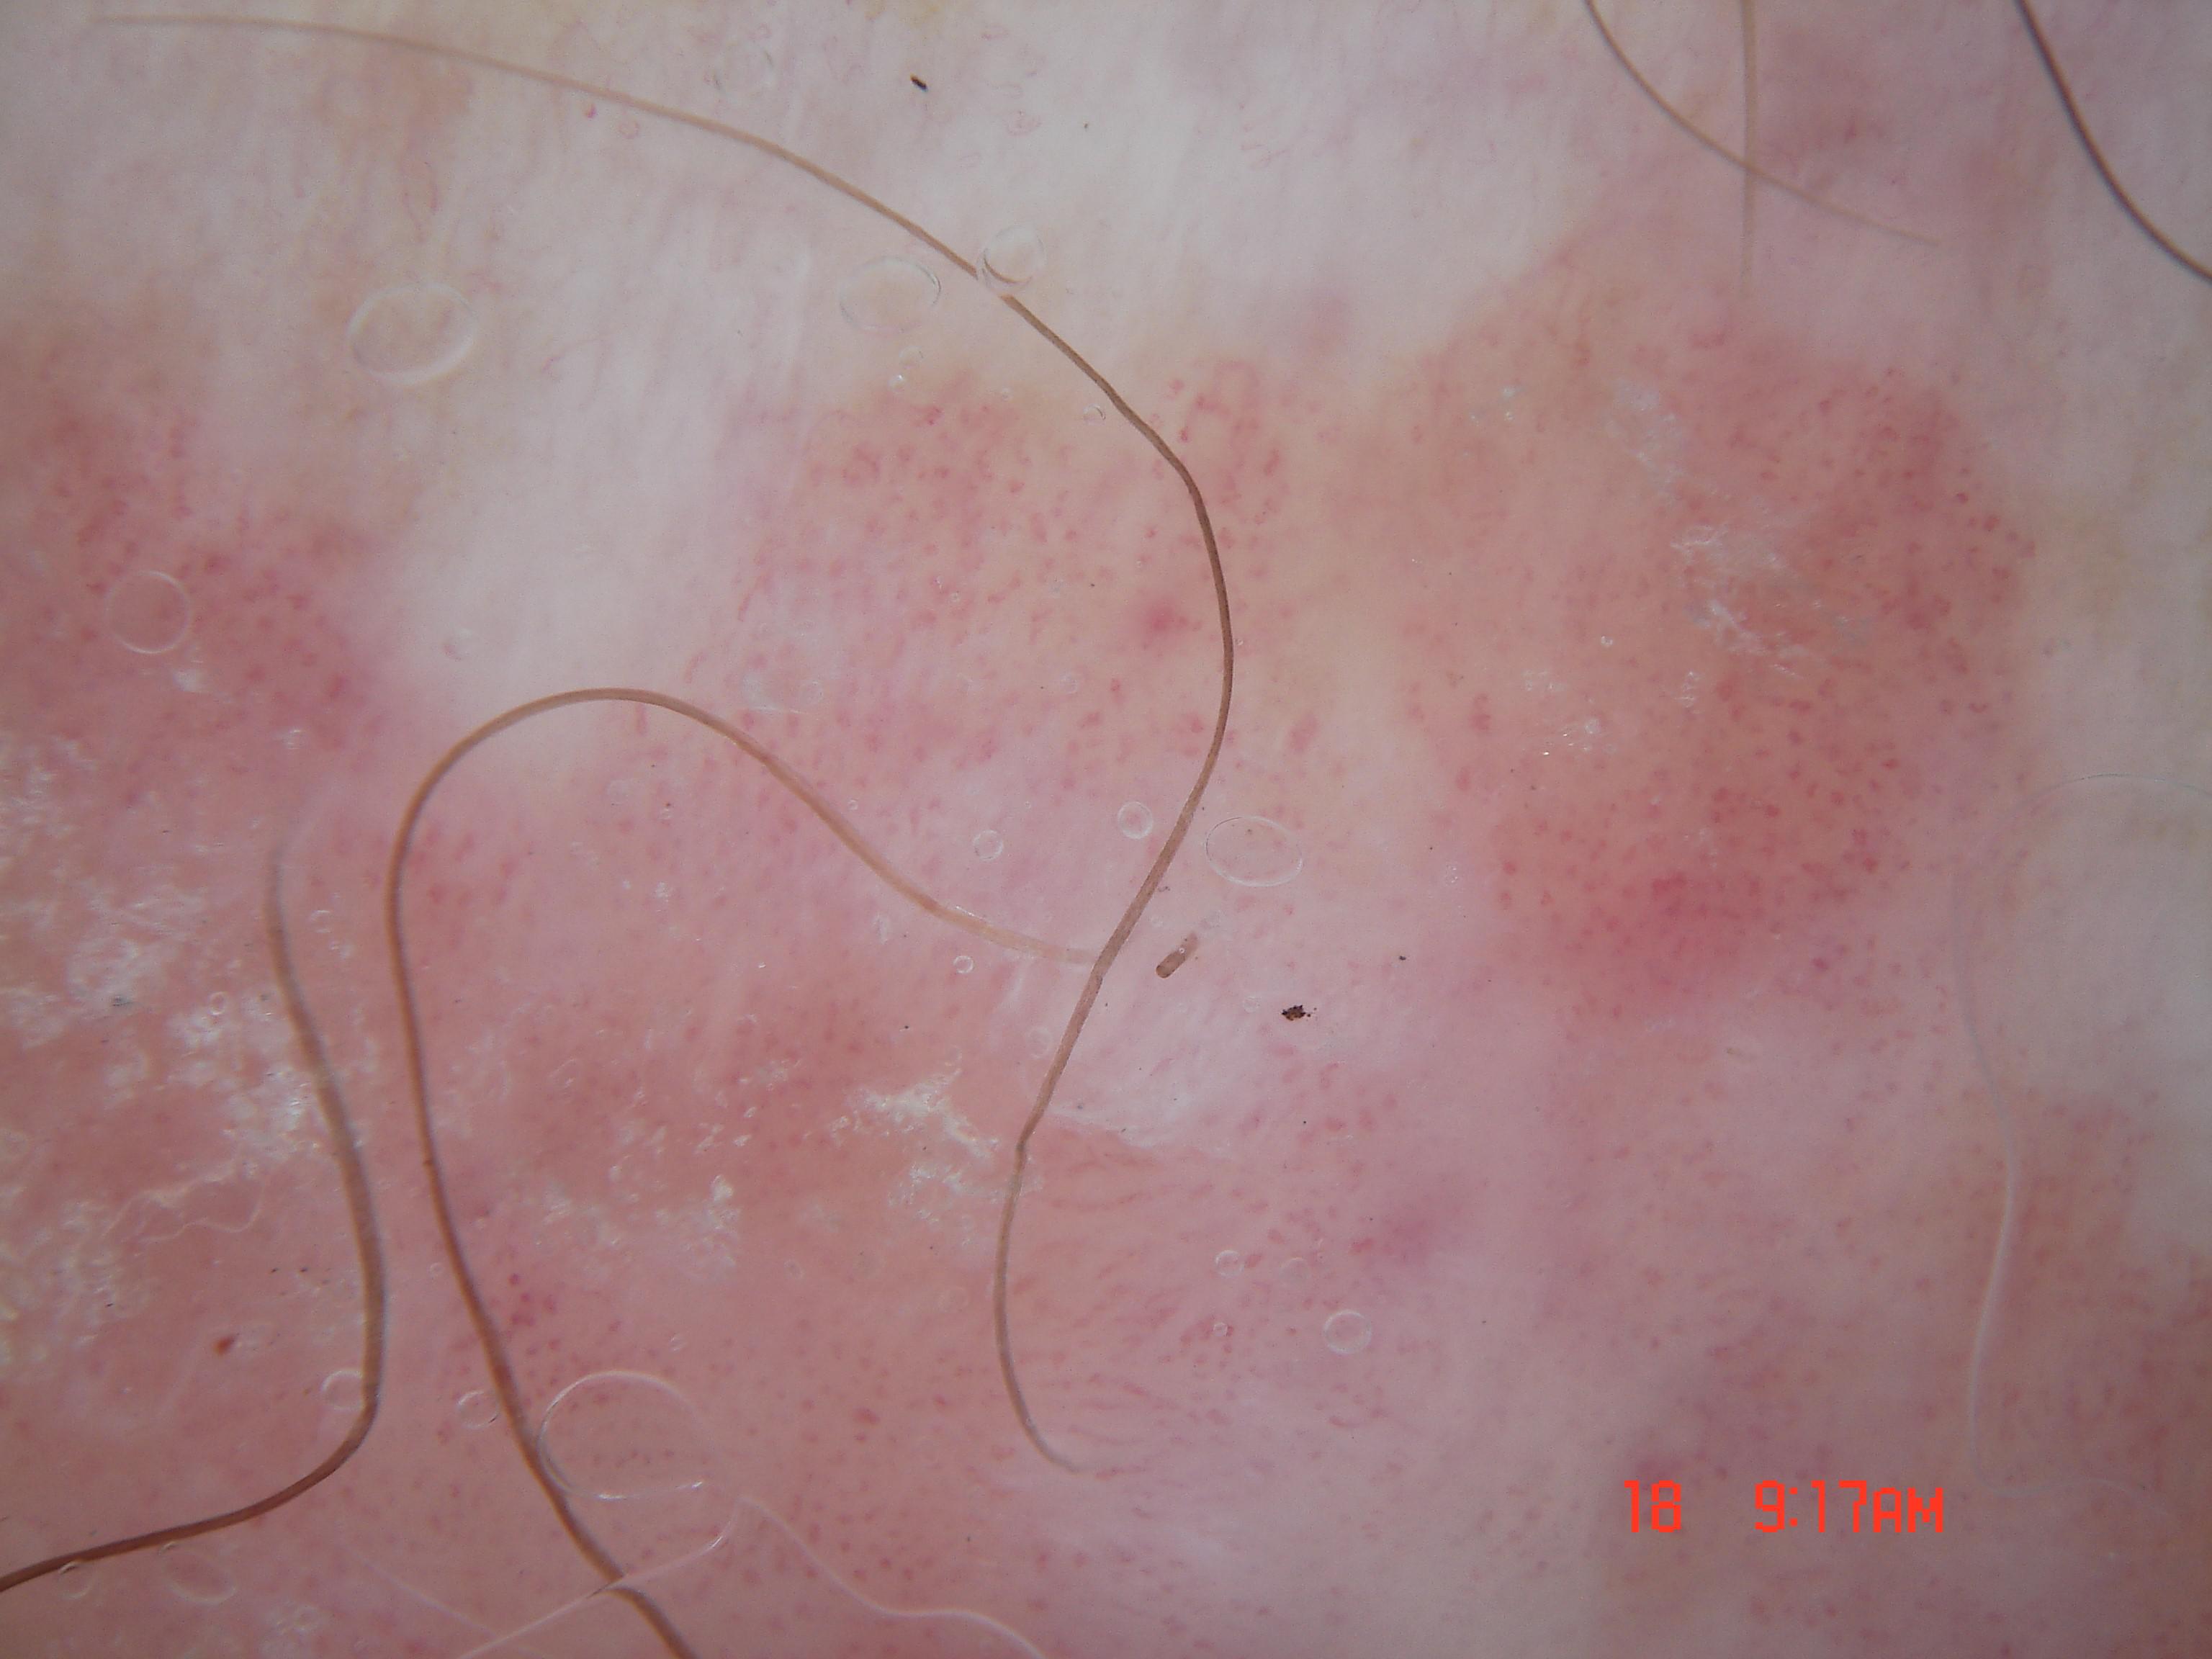

{

"age_approx": 60,

"anatom_site_general": "lower extremity",

"concomitant_biopsy": true,

"dermoscopic_type": "contact non-polarized",

"diagnosis_1": "Indeterminate",

"diagnosis_2": "Indeterminate melanocytic proliferations",

"diagnosis_3": "Atypical melanocytic neoplasm",

"diagnosis_confirm_type": "histopathology",

"family_hx_mm": false,

"image_type": "dermoscopic",

"melanocytic": true,

"patient_id": "IP_6941577",

"personal_hx_mm": false,

"sex": "female"

}